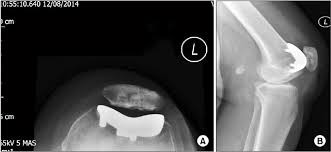

La Prótesis Femoropatelar de Rodilla.

La prótesis parcial femoropatelar de la rodilla es una prótesis especial que está indicado en pacientes con un desgaste muy inicial y con un patrón que afecta solo el compartimiento anterior de la rodilla. Típicamente, son pacientes con dolor en la parte de delante de la rodilla al estar sentados o al subir o bajar escaleras. No les molesta al caminar sobre un terreno plano sin desnivel. Tiene la ventaja de resecar mucho menos hueso del paciente, así preservando más hueso para el futuro. Además, al mantener la parte biológica del cartílago y la ligamentosa de los cruzados de la rodilla, parece conservar mucho mejor la sensibilidad y la marcha de la rodilla (la propiocepción). También la recuperación de esta cirugía (al ser menos agresiva) es más rápida.

|  |  |

Los mejores resultados de supervivencia se ven en pacientes con poca enfermedad y poca deformidad del aparato extensor, mayor de edad o con normo/bajo peso. Los pacientes candidatos a esta protesis probablemente no son más de 2-3 % del total de pacientes con artrosis de la rodilla. Además, su uso es restringido debido a la probabilidad de la progresión de a enfermedad dentro del resto de la articulación, que puede ser generador del dolor y fracaso de la prótesis con el paso de los años. Por tanto, cuando se decide por optar por este implante precisa un consenso claro entre el cirujano y el paciente entendiendo todos los variables que puedan surgir. Siempre que se plantea colocar una protesis femoropatelar habitualmente también se tiene preparado la protesis total por si el grado de enfermedad comprobado durante la cirugía es más de la prevista antes de la cirugía.